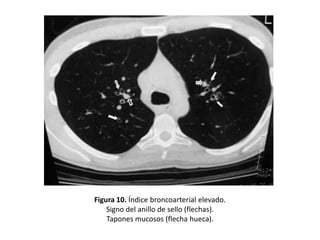

• Dilatación bronquial:

– Presencia de un diámetro bronquial interno mayor

que el de la arteria bronquial adyacente. (Índice

broncoarterial)

– En el caso de las BQ es, por lo tanto, mayor de 1.

• Cuando el bronquio transcurre perpendicular al

plano de sección, esta dilatación da lugar al

“signo del anillo de sello”:

– El bronquio dilatado forma un anillo y la arteria

acompañante, el sello. (Figura 10)

Figura 10. Índice broncoarterial elevado.

Signo del anillo de sello (flechas).

Tapones mucosos (flecha hueca).